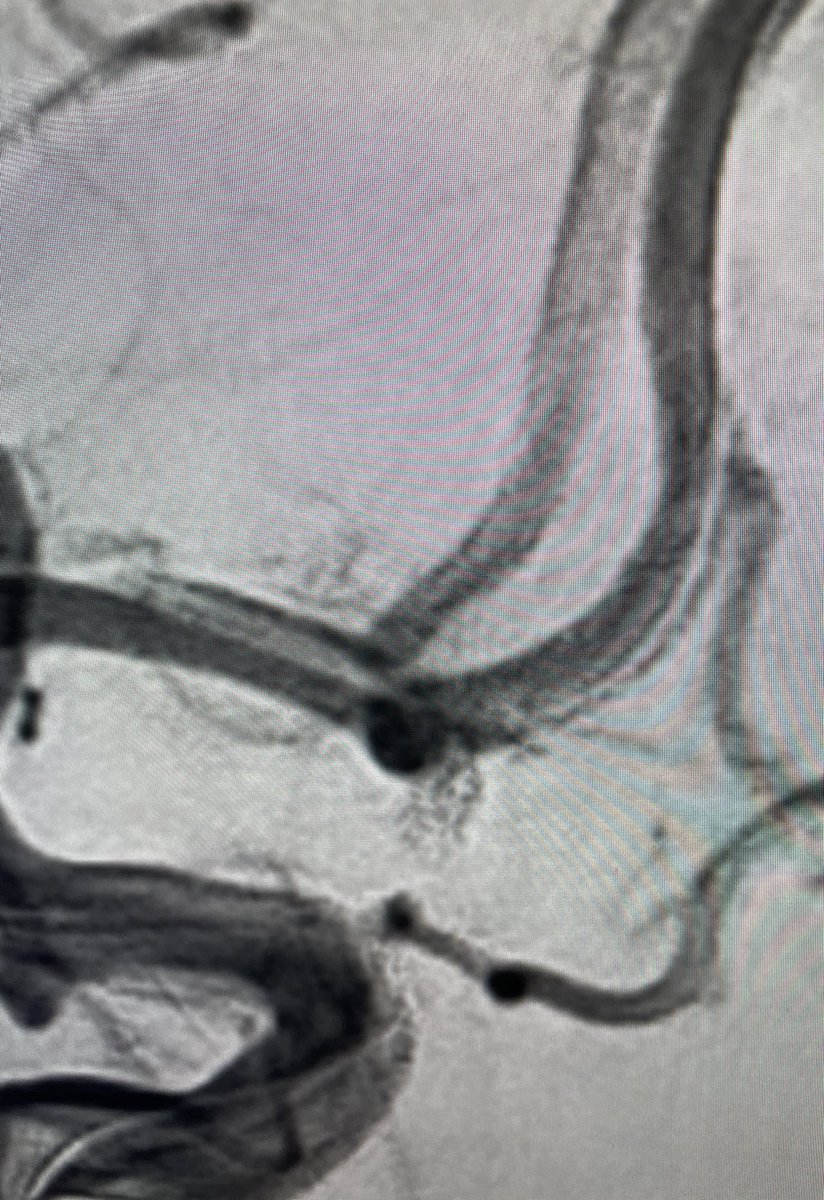

El Dr. Carlos Pérez@Justcharly9, nos resume en menos de 15 minutos los dos principales ensayos clínicos que comparan tratamiento Endovascular VS Quirúrgico (ISAT, IBRAT) de aneurismas rotos.